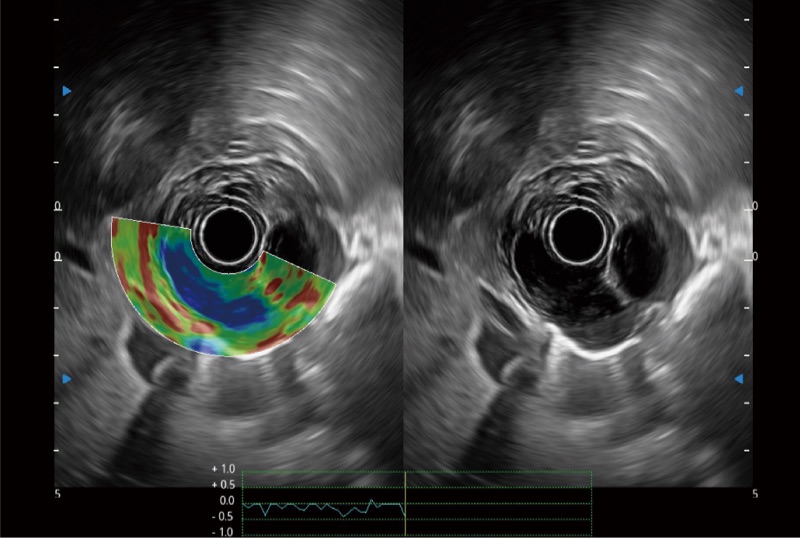

位移矫正技术

不可靠区域自动剔除

弹性定量分析软件